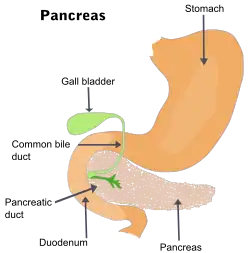

| The pancreas and surrounding organs | |

Pancreatitis is a condition characterized by inflammation of the pancreas.[1] The pancreas is a large organ behind the stomach that produces digestive enzymes and a number of hormones.[1] There are two main types: acute pancreatitis, and chronic pancreatitis.[1]

The two most common causes of acute pancreatitis are a gallstone blocking the common bile duct after the pancreatic duct has joined; and heavy alcohol use.[1] Other causes include direct trauma, certain medications, infections such as mumps, and tumors.[1] Chronic pancreatitis may develop as a result of acute pancreatitis.[1] It is most commonly due to many years of heavy alcohol use.[1]